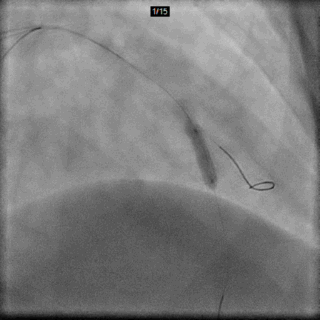

Cx Wire (Anchor)

以CAU体位的造影静态图为路标,送入回旋支导丝

LAD Wire

先后以CAU及CRA体位的造影静态图为路标,送入前降支导丝

D1 Wire

以CRA体位的造影静态图为路标,送入对角支导丝